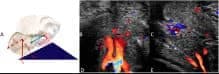

À l’aide d’un appareil d’échographie, les chercheurs ont étudié un couple volontaire pendant qu’ils réalisaient cinq positions sexuelles populaires pour une période de 10 minutes.

Les cinq positions choisies pour l’étude étaient le missionnaire avec la femme sur le dessus, le missionnaire avec l’homme sur le dessus (avec et sans oreiller), assis face à face et la levrette.

Les échographies démontrent que la levrette est la position qui offre le moins de contact direct avec le clitoris, ce qui fait en sorte qu’elle produit moins d’afflux sanguins que la position du missionnaire avec oreiller.